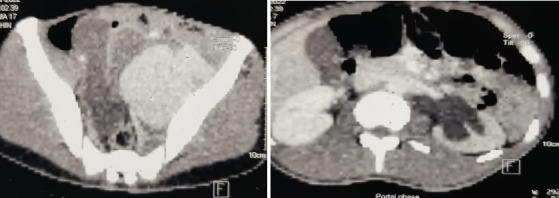

Isolated internal iliac artery aneurysm (IIIAA) is a rare condition, with limited information available about its symptoms and surgical treatment outcomes, particularly in Ghana. This case report presents the 4-year surgical treatment outcomes of three patients (aged 42, 58, and 22 years) with IIIAA, each exhibiting different clinical presentations. All patients experienced pelvic pain and difficulty walking but had uneventful post-operative recoveries. They made significant progress with physiotherapy and were able to mobilise with a Zimmer frame before discharge. Currently, all three patients are mobilising unaided, and post-operative Computed Tomography (CT) scans show no complications. This report highlights the importance of early diagnosis to minimise complications and improve the prognosis for IIIAA, which often presents asymptomatically and can manifest with a wide range of clinical findings. The study underscores the effectiveness of open surgical repair in achieving positive outcomes for IIIAA patients in Ghana.